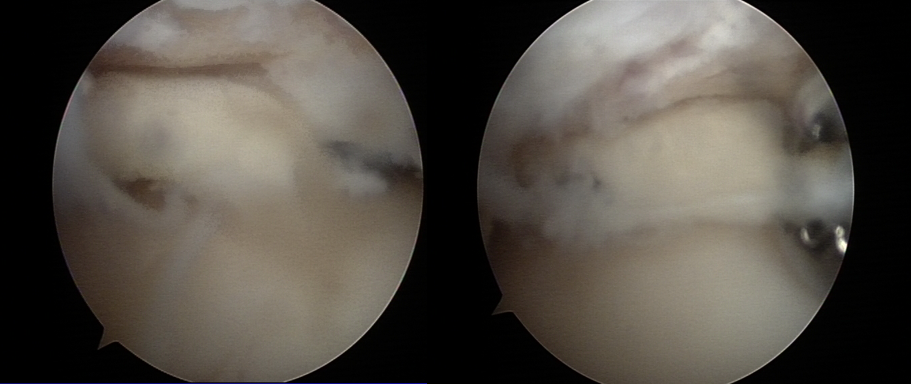

软骨退变

游离体形成

关节清理术后

清除的骨赘及游离体